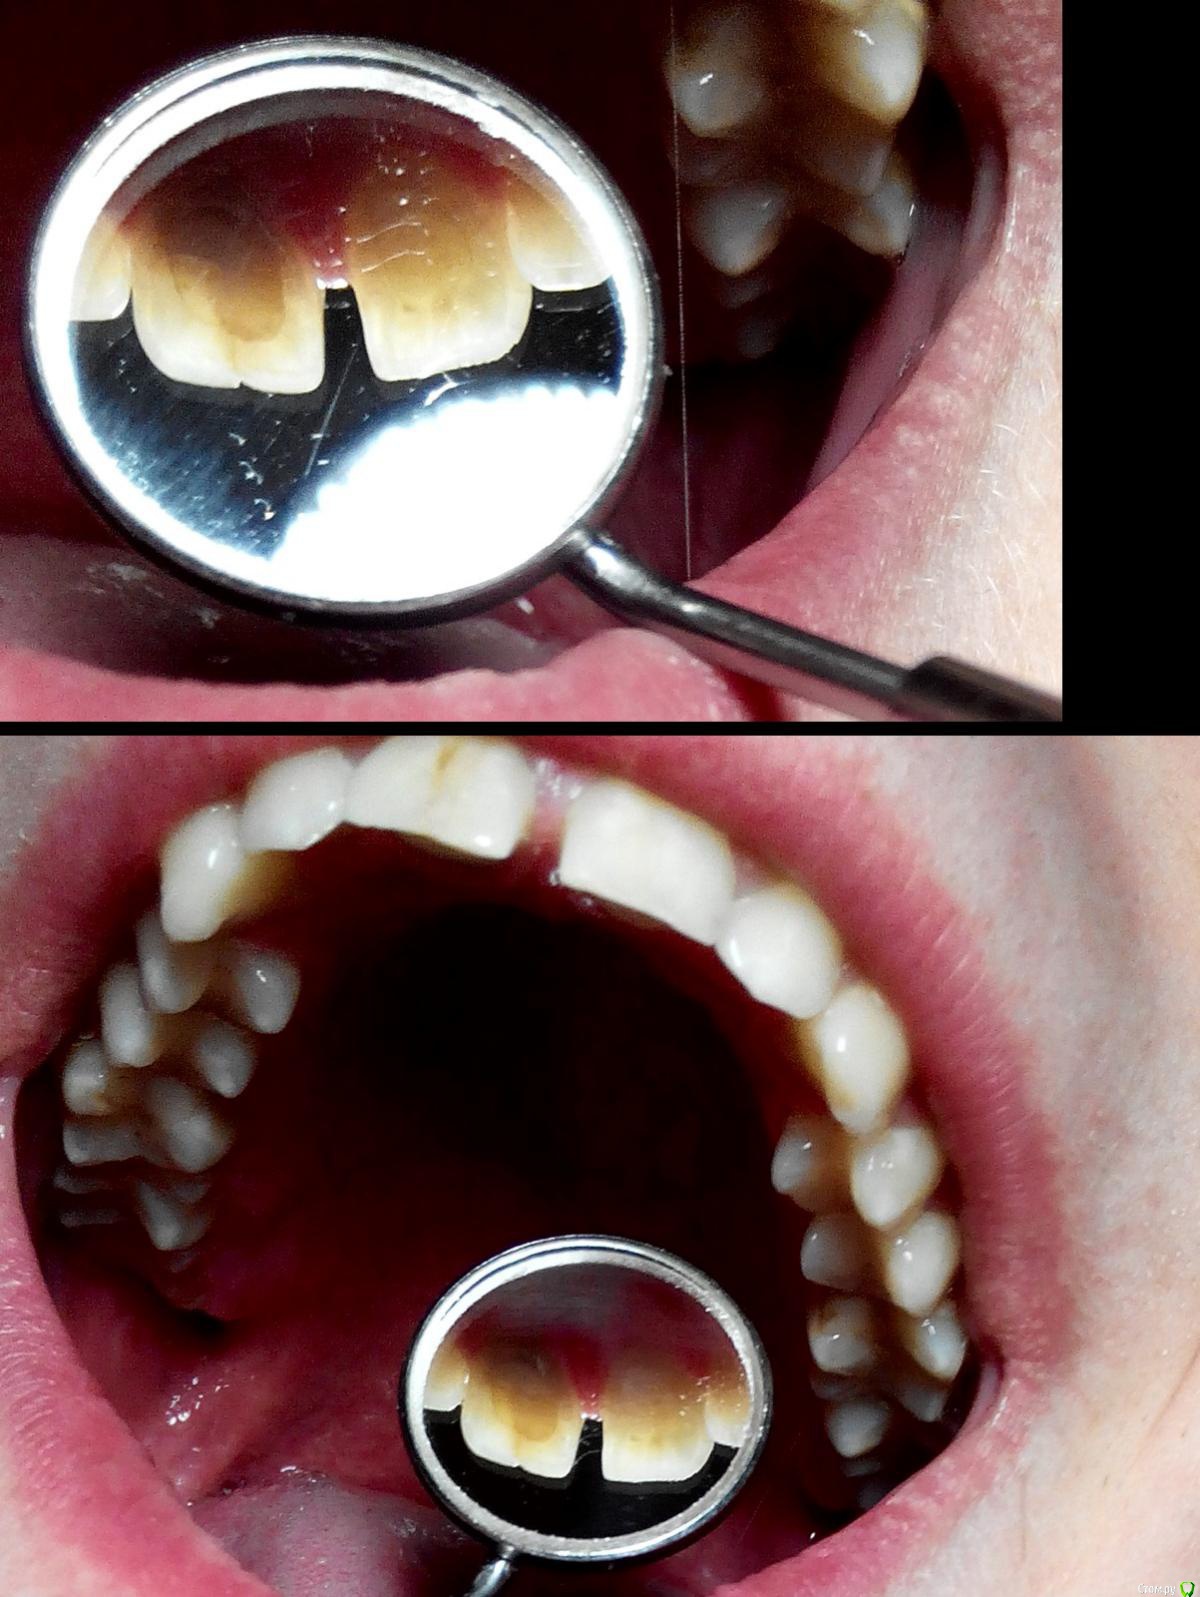

Alex397 Опубликовано 16 февраля, 2015 Поделиться Опубликовано 16 февраля, 2015 Здравствуйте! Подскажите пожалуйста по след. ситуации.Стоматолог сказал что два верхних резца требуют немедленного лечения каналов с последующей установкой коронок на оба зуба. Вопрос следующий: стоит ли устанавливать коронку на левый резец после лечения канала? Стоматолог аргументирует это тем, что это не зуб, а скорлупа и что он в любой момент может под основание отколоться и что потом спасти будет нельзя. Как вы считаете, есть ли такая необходимость? Ссылка на комментарий

SDC Опубликовано 16 февраля, 2015 Поделиться Опубликовано 16 февраля, 2015 На левый центральный резец может быть и стоит сделать коронку, но это второстепенный вопрос.Первично стоит рассмотреть вопрос удаления правого центрального резца с замещением имплантатом и коронкой по причине наружной резорбции/кариеса корня 11 зуба 4 Ссылка на комментарий